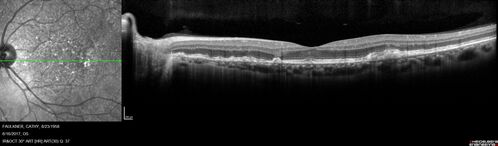

Soft Drusen

63 year old female with 20/16 vision both eyes